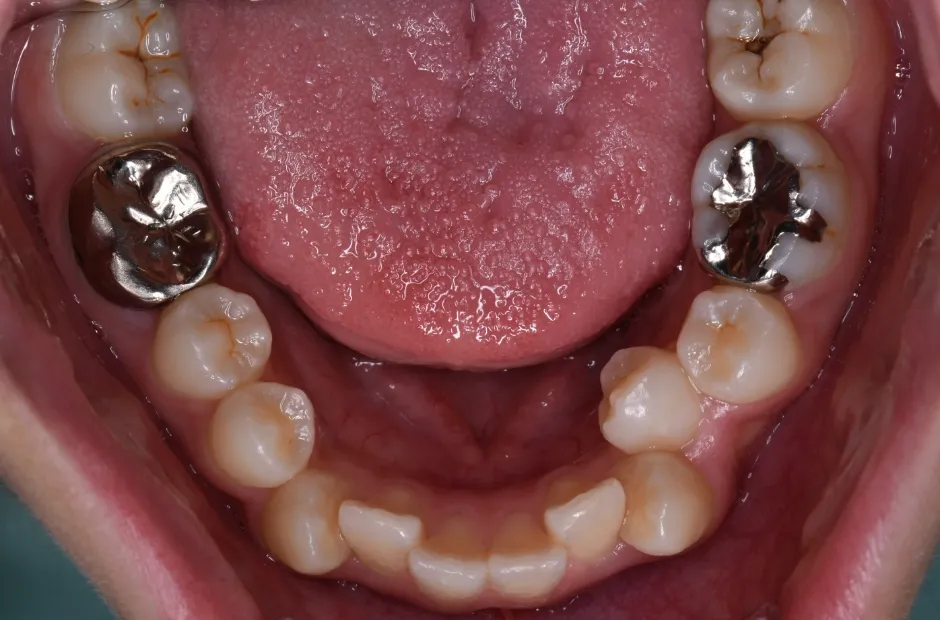

治療症例

ブラケット矯正

前歯部反対咬合

| 診断名・主訴 | 前歯部反対咬合 |

|---|---|

| 年齢・性別 | 14歳・男性 |

| 治療期間・回数 | 1年2か月 |

| 治療に用いた主な装置 | ブラケット矯正 |

| 抜歯部位 | なし |

| 治療費 | 60万円(税抜) |

| リスク・副作用 | 装置による違和感・疼痛・歯肉退縮・歯根吸収・虫歯のリスクなど |

治療前